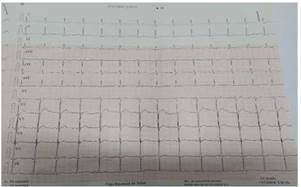

Cuatro meses después del cuadro inicial, el paciente fue hospitalizado nuevamente por cuadro de 4 horas de evolución caracterizado por presentar parálisis flácida de miembros superiores e inferiores, acompañado por parestesias en miembros inferiores, mialgias y disnea, sin alteración de funciones superiores, al examen físico con presión arterial 110/70, frecuencia cardíaca 90 latidos por minuto, tiroides de tamaño normal, sin alteraciones cardiopulmonares, sin temblor distal en manos. Entre los estudios de laboratorios realizados en emergencias destacó la presencia de hipopotasemia severa de 2,0 mEq/l. Con la sospecha de PPHT, se solicitó estudios de función tiroidea con resultados de TSH 0,01 uUI/ml (rango de referencia 0,4 y 4,5), T4 libre 3,09 ng/ dl (rango de referencia 0,8 y 1,65), anticuerpos anti TPO 552 UI/ml (rango de referencia 0 a 95) y anti tiroglobulina 211 UI/ml (rango de referencia 0 a 30), tiroglobulina 17 ng/ml (rango de referencia 0 a 55), ecografía tiroidea que reportó de tamaño y morfología normal, sin evidencia de lesiones nodulares (Figura 1), electrocardiograma sin alteraciones (Figura 2). Se inició tratamiento con fármacos antitiroideos y betabloqueadores, además de jarabe de potasio, el mismo que se disminuyó de forma gradual hasta su suspensión. Hasta la fecha el paciente mantiene tratamiento con tiamazol 20 mg por día, con control adecuado de la función tiroidea, sin nuevos episodios de debilidad y/o hipopotasemia. Se presenta la evolución de la concentración de potasio sérico en el Figura 3.

Figura 2. Electrocardiograma realizado al ingreso en la segunda hospitalización: normal, ritmo sinusal, P-R Normal, sin alteraciones de repolarización sin onda U isquemia o neurosis.